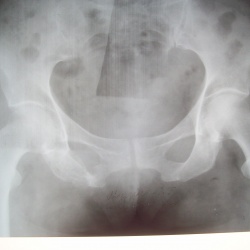

Травма. Пациент направлен на рентгенографию тазобедренного сустава.